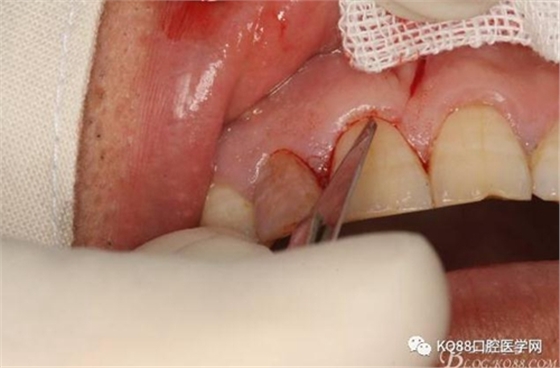

圖6.行唇側(cè)角形切口(11近中垂直切口+齦溝內(nèi)水平切口)垂直切口距離前庭溝約1~2mm。這樣可以減輕術(shù)后腫脹。

圖7. 角形切口中的齦溝內(nèi)切口情況:11號(hào)刀片伸進(jìn)齦溝內(nèi)斜切。